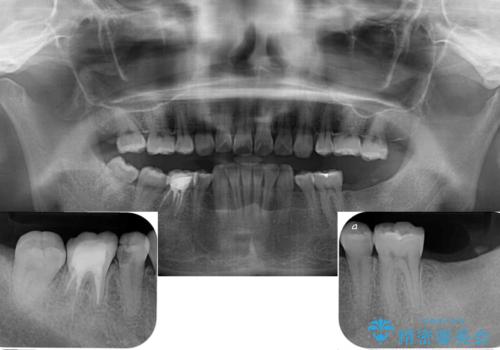

- 左下欠損部のインプラント治療と、右下の歯の痛みを気にして来院された患者様です。

左下の欠損部は、世界中で高い信頼を得ているストローマンインプラントを用いて治療を行うこととしました。

ただし、長期間欠損を放置していたことで、咬み合う上の奥歯が動いてしまっていたので、まずは上顎奥歯の部分矯正を行い、より理想的な咬み合わせを目指すこととしました。

右下の歯は、レントゲン上歯髄組織まで虫歯が及んでいるように見えましたが、痛みの症状は強くなかったため、歯髄組織の一部を断ち歯根部分の組織を保存する生活歯髄療法を第一選択に処置を進めて行くこととしました。

まず生活歯髄療法を行い、その後部分矯正やインプラント処置を行いましたが、最初の処置から1年以上経っても右下奥の処置歯の神経組織に異常は認められませんでした。